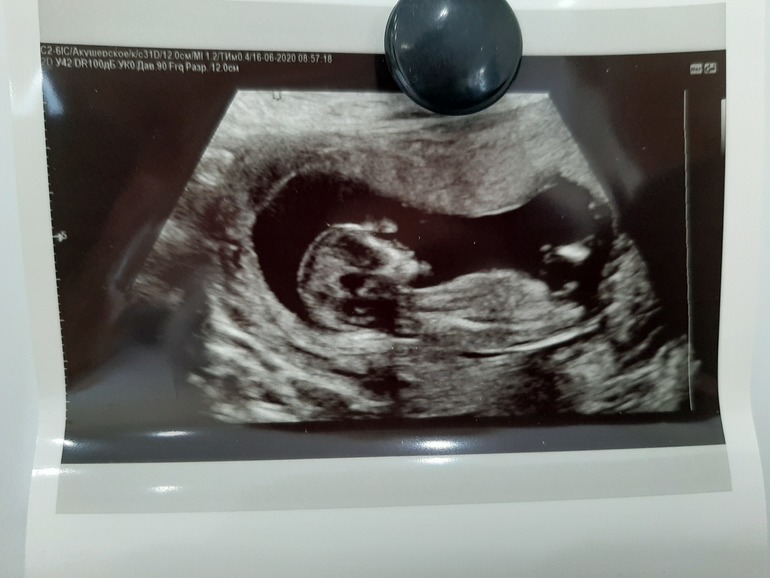

И я туда же!)) Кто сможет определить пол?

Пол малыша

Я даже и не знала, что по фото можно определить пол, сейчас загуглила и узнала) По мне так девочка.

Кто-то смирненько там лежит😍руки по швам))солдатик или солдатка!Дорогая пока что мне похоже на мальчика,но очертания головы похожы на девочку!Ещё чуть и узнаешь точно)))

Я за девочку. От подписана на одну узистку, она не ошибается. И вот в сторицей у неё был бугорок параллельно а кончик приподнят, и оказалось это мальчик.